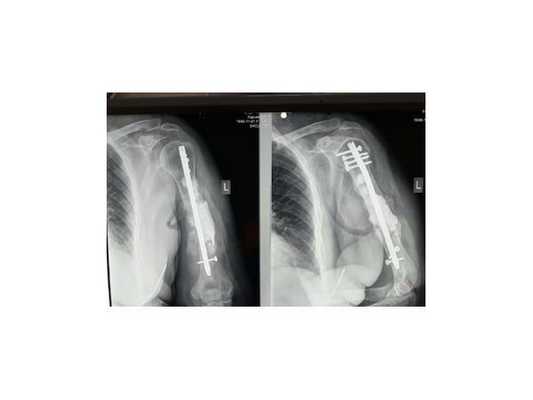

- Первый этап — пластика дефекта по Маскуле. Отломки фиксировали антеградно интрамедуллярным стержнем. Вокруг стержня на протяжении всего дефекта сформировали цементную мантию с добавлением 2 г. Ванкомицина. Мягкие ткани и рану ушили. Послеоперационный период прошёл гладко.

- Через пять недель провели второй этап лечения. Из гребня подвздошной кости взяли губчато-кортикальный аутотрансплантат 7 х 2 х 3 см. Выполнили разрез по переднему отделу плеча над плечевым суставом. Стержень удалили. Вокруг цементной мантии сформировалась биологически активная мембрана. Её аккуратно отслоили. В неё уложили аутотрансплантат, мембрану над ним ушили. Таким образом, костный дефект между отломками был заполнен губчато-кортикальным аутотрансплантатом. Отломки фиксированы пластиной LCP PHILOS. Рана ушита. Послеоперационный период прошёл без осложнений.